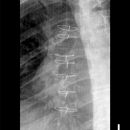

Hemithorax a.-p.

1.-7. Rippe: Inspiration, oberes Licht Prominenz

8.-12. Rippe: Exspiration, 1 QF oberhalb Beckenkamm

Die Rippen müssen vollständig abgebildet sein.